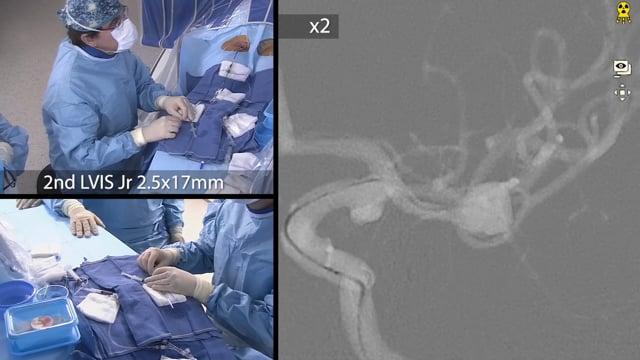

One&Done technique with optiMAX large volume coil

Stent assisted coilingAneurysms